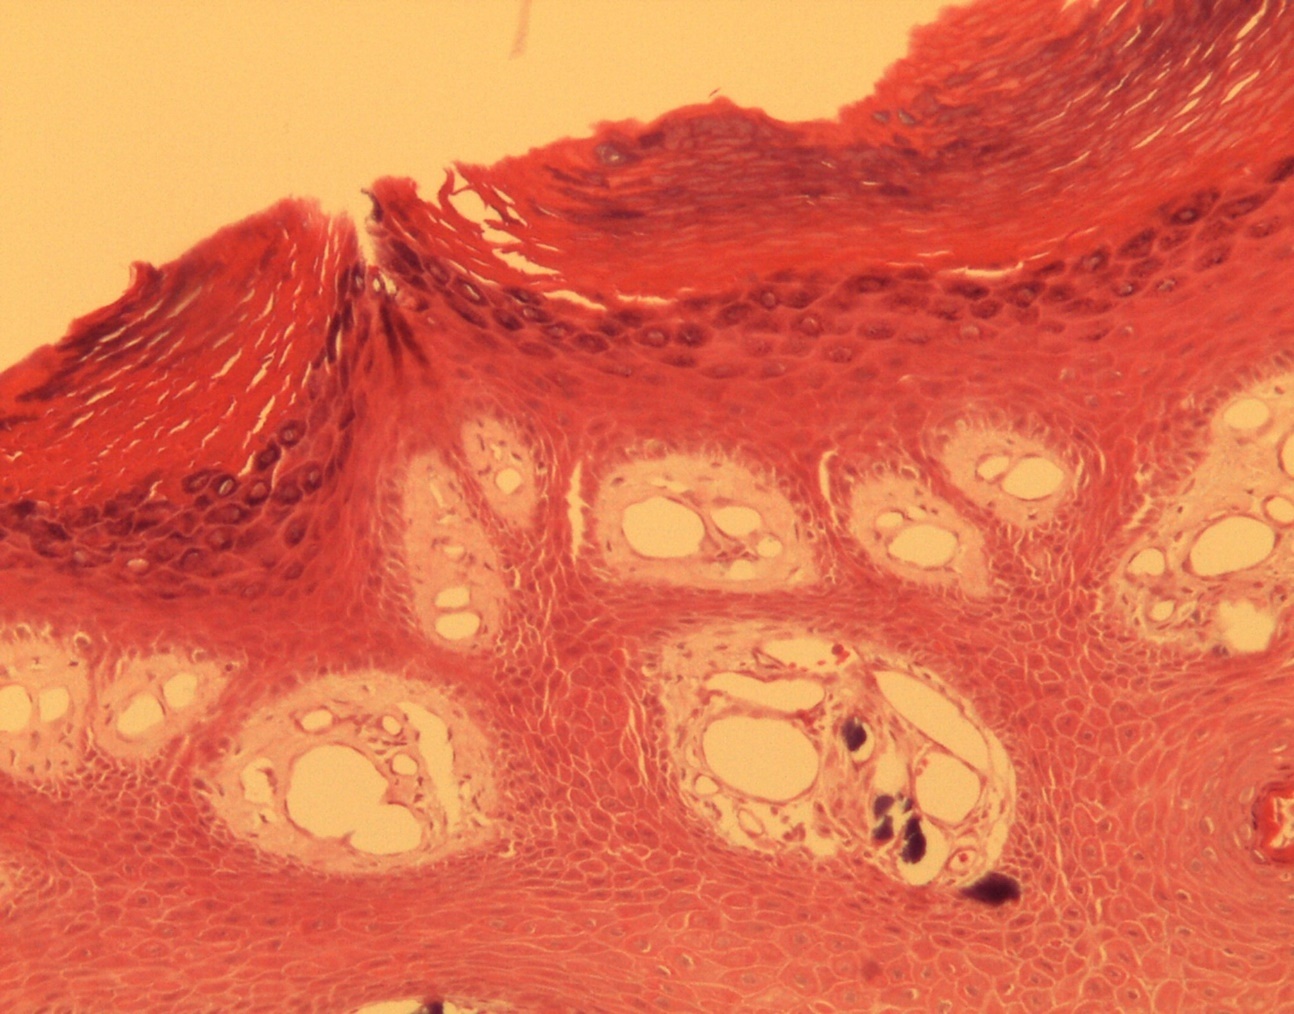

A 9-year-old male patient who was treated in the dermatology service for a progressively growing keratotic nummular dermal lesion on the right knee. With the clinical judgment of viral wart, the lesion was removed. In the Pathology Service, a nummular keratotic lesion of 0.5 cm in maximum dimensions was received, which crackled when cut. Figure 1, Figure 2, Figure 3, Figure 4, Figure 5

Figure 2.Common wart with calcium foci at the level of the dermal vessels grouped in lobules. HE. 200x.